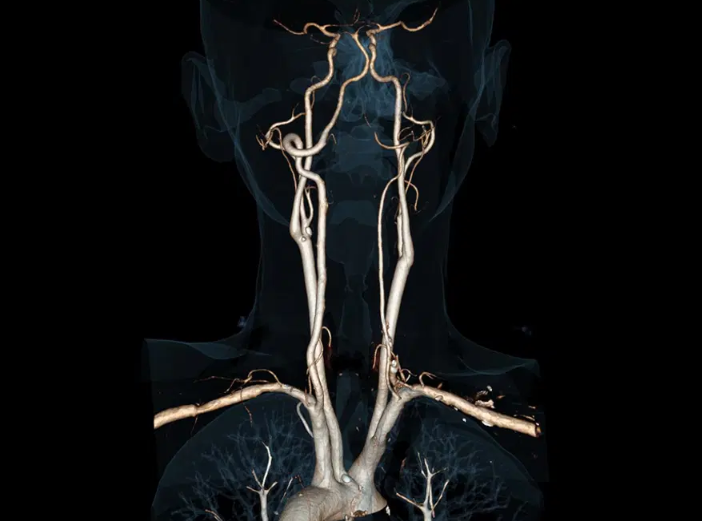

- Vascular: redução de artefatos metálicos e análise de estents;